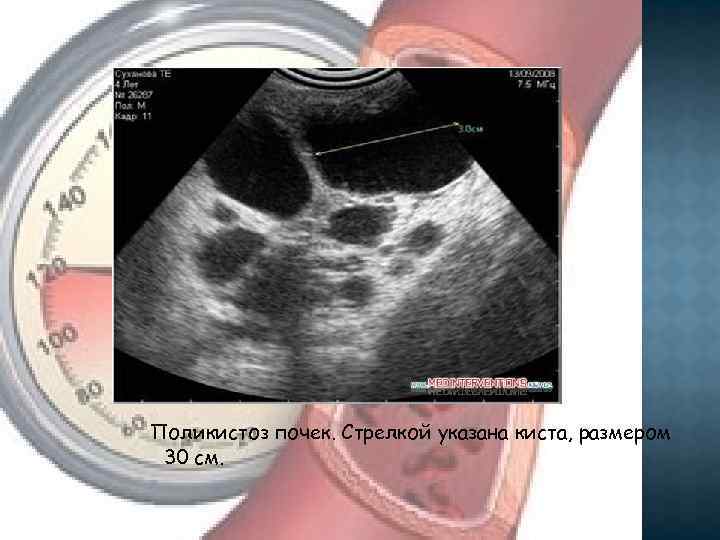

ПОЛИКИСТОЗ ПОЧЕК Поликистоз почек является распространенной патологией и составляет 12 -14 % всех заболеваний почек. Кисты могут обнаруживаться в любом участке почек. Они могут быть одиночными или множественными, по мере прогрессирования болезни количество их возрастает, размер увеличивается.

Поликистоз почек. Стрелкой указана киста, размером 30 см.